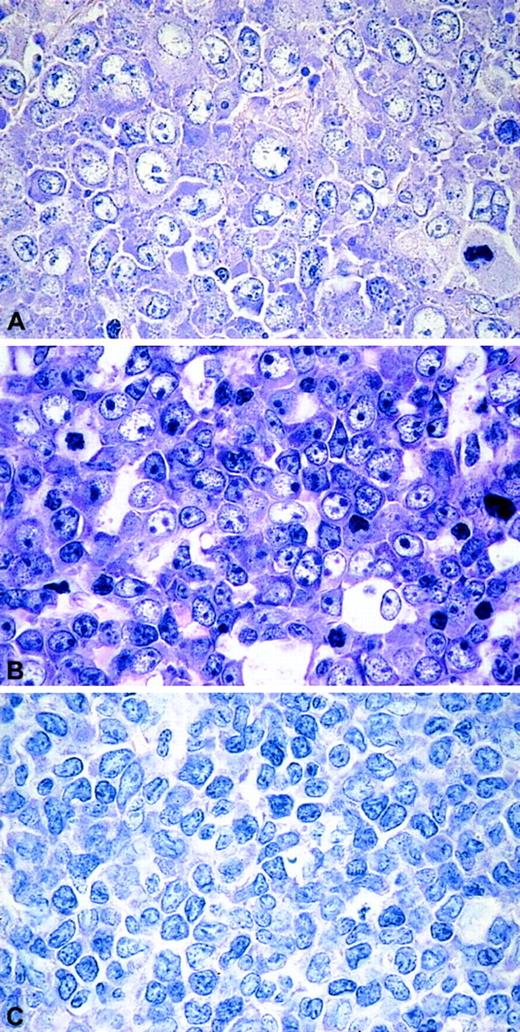

On morphology, the series presented here displayed a remarkable heterogeneity. The CD5+ DLBLs consisted of 8 centroblastic and 3 immunoblastic DLBLs. Two tumors (cases 9 and 10) displayed particular features: their neoplastic cells were medium- to large-sized with scant cytoplasm and slightly irregular nuclei, giving the morphologic impression of blastoid MCL (Figure1). All cases were CD5+ and negative for CD23 and CyclinD1. IgD expression was found in 5 of 13 (39%) CD5+ tumors. In the CD5− DLBLs, 8 of 39 cases tested were IgD+ (difference not statistically significant). Cases 6 and 12, in addition, stained weakly for CD10. Nuclear expression of BCL6 was demonstrated in more than 10% of cells in 12 of 12 CD5+ DLBLs and in 46 of 54 (85%) CD5− DLBLs. There was also no statistically significant difference between the groups, if only high BCL6 expression (> 60% of cells) was taken into account (4 of 12 [33%] CD5+DLBL versus 29 of 54 [54%] CD5− DLBL).

The morphologic spectrum of CD5+DLBLs.

(A) DLBL centroblastic. (B) DLBL immunoblastic. (C) DLBL unclassified. Giemsa stain, original magnifications × 400.